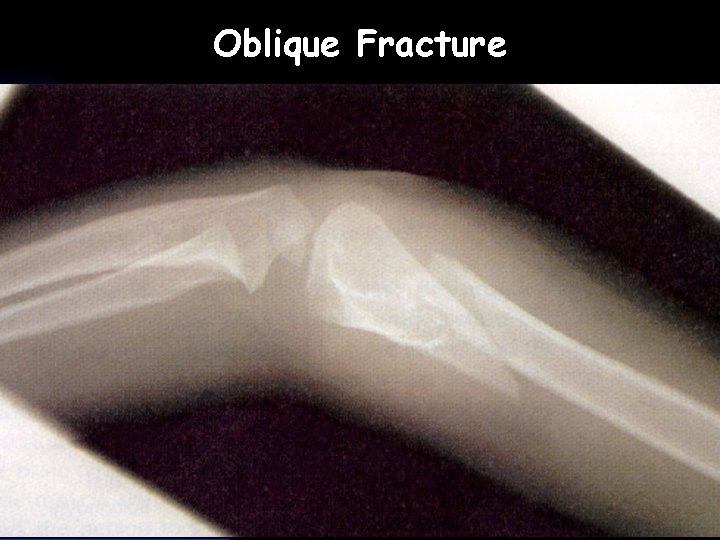

Oblique Fracture